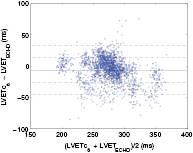

The agreement between  and

and  was also analyzed using regression plots (figure 10) and a Bland–Altman plot (figure 11). Error distributions were tested for Gaussianity by using the Kolmogorov–Smirnov test. Accordingly, statistical analysis was performed using the paired Student test and the two-sided Wilcoxon signed rank test and the values shown in table 4 have been found to be statistically relevant (p < 0.001).

Standard image High-resolution imageFigure 11. The Bland–Altman plot of the measured (LVETc6) and reference LVET using the proposed algorithm in the global dataset.

The agreement between the LVETc6 and LVETECHO was also assessed via Bland–Altman plot, presented in figure 11 for the global dataset. The horizontal solid line represents the mean error while the dashed lines denote the level of agreement between LVETc6 and LVETECHO, i.e. mean ± standard deviation and mean ±2 standard deviation. One can observe that the average error is close to zero and the estimation error is not evenly distributed around the whole range of LVET values, particularly in the higher range where a greater dispersion is shown.